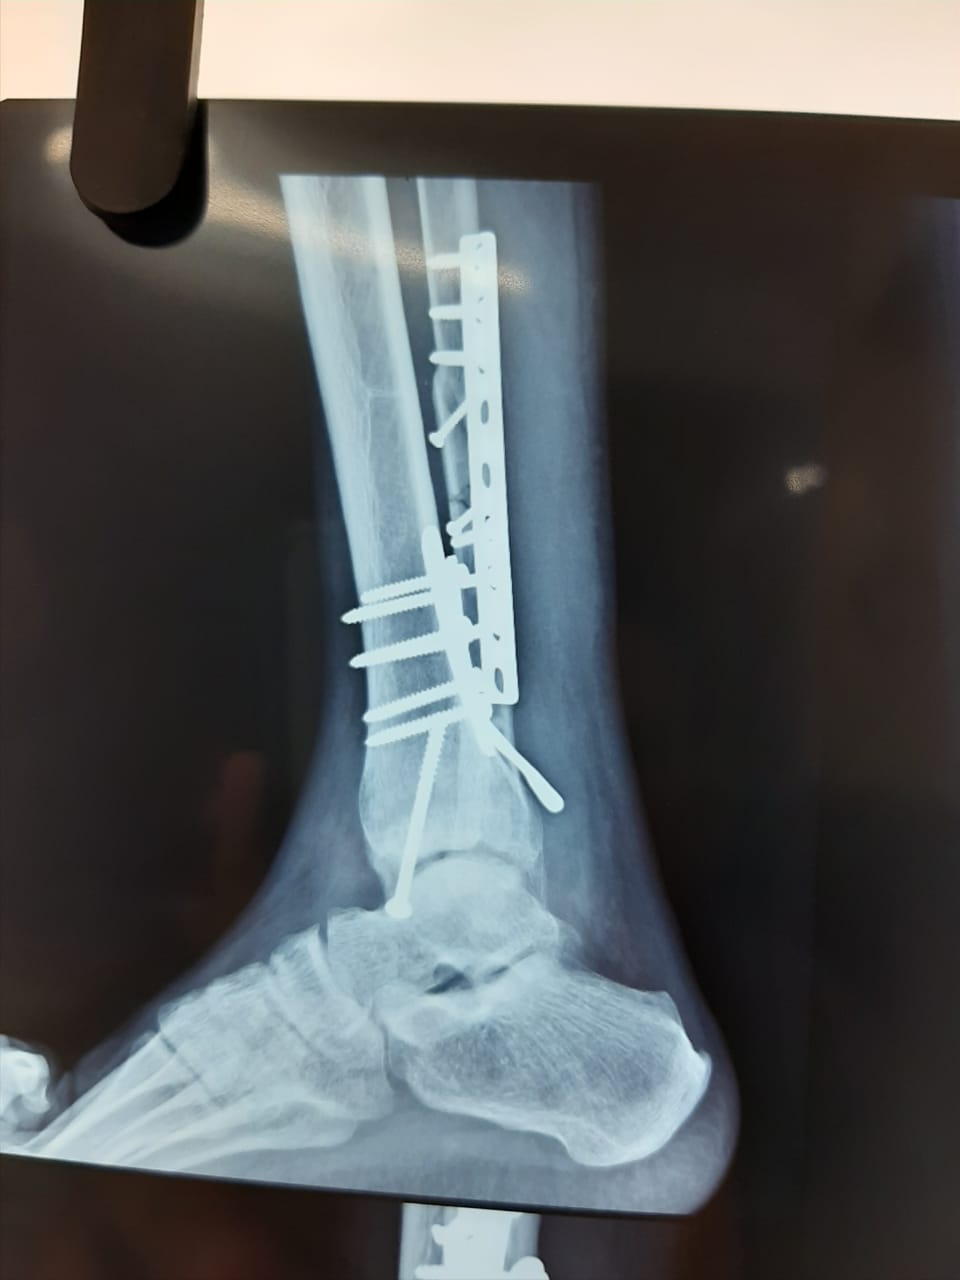

Complex Atypical Rotational Ankle Fracture Surgery

Dr Girish Motwani, one of the best foot surgeon in Nagpur, treated successfully a 30 year old guy with a history of a road traffic accident. He had...